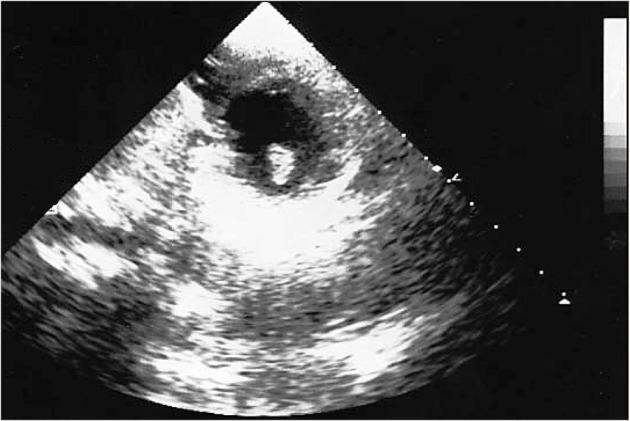

There are still no guidelines about pediatric cardiac cancers. The purpose of this work is to provide new scientific data facilitating the differential diagnosis of a rare cardiac tumor with an unusual presentation, such as the cardiac inflammatory myofibroblastic tumor (IMT). A 3-year-old male child presented with several symptoms including unconsciousness, vomiting, and drowsiness. A clinical and neurological examination revealed a unilateral (right) motor delay and positive unilateral Babinski sign. Electrocardiogram (ECG) was normal. The total body computed tomography (CT) scans showed hypodensity in the left temporal-parietal lobe, a large hypodense area in the right frontal lobe, and a second area in the left frontal lobe were found with head CT. A magnetic resonance (MR) also noted cerebral areas of hypointensity. The echocardiographic images revealed an ovoid mass, adherent to the anterolateral papillary muscle. The histological exams, performed with hematoxylin-eosin, Masson's trichrome, Alcian blue PAS, Weigert and Van-Gieson stain, allowed observing the microscopic structure of the neoplastic mass. The immunohistochemical analysis was performed through subsequent antibodies: anti-vimentin, anti-actina, anti-ALK, anti-CD8, anti-CD3, anti-CD20, anti-kappa and lambda chains, and anti CD68 antibodies. The healthcare professionals diagnosed a cardiac IMT with brain embolism. The ventricular localization, observed through radiological exams, required a differential diagnosis with fibroma and rhabdomyoma, the presence of brain embolism with sarcoma, and its morphology with fibroma. Neurological symptoms might be attributed to encephalitis, primitive cerebral cancer, such as astrocytoma or neuroblastoma, cerebral metastases due to any malignancy, or embolic stroke. New studies are encouraged to better define IMT behavior and draw up guidelines confirming the crucial role of multidisciplinary approach and treatment protocol selected on the basis of the characteristics of the tumors, in the case of this rare type of cancer.

目前仍没有关于儿童心脏肿瘤的指南。这项工作的目的是提供新的科学数据,以促进对一种表现不寻常的罕见心脏肿瘤,如心脏炎性肌纤维母细胞瘤(IMT)的鉴别诊断。一名3岁男童出现了包括昏迷、呕吐和嗜睡在内的多种症状。临床和神经学检查发现单侧(右侧)运动迟缓以及单侧巴宾斯基征阳性。心电图(ECG)正常。全身计算机断层扫描(CT)显示左侧颞顶叶低密度,右侧额叶有一大片低密度区,头部CT还发现左侧额叶有第二个区域。磁共振成像(MR)也显示脑区有低信号。超声心动图图像显示一个椭圆形肿块,附着于前外侧乳头肌。通过苏木精-伊红染色、马松三色染色、阿尔辛蓝过碘酸雪夫染色、魏格特染色和范吉森染色进行组织学检查,得以观察肿瘤肿块的微观结构。免疫组织化学分析通过后续抗体进行:抗波形蛋白抗体、抗肌动蛋白抗体、抗间变性淋巴瘤激酶(ALK)抗体、抗CD8抗体、抗CD3抗体、抗CD20抗体、抗κ和λ链抗体以及抗CD68抗体。医护人员诊断为心脏IMT伴脑栓塞。通过影像学检查观察到的心室定位需要与纤维瘤和横纹肌瘤进行鉴别诊断,脑栓塞的存在需要与肉瘤进行鉴别诊断,其形态需要与纤维瘤进行鉴别诊断。神经症状可能归因于脑炎、原发性脑癌,如星形细胞瘤或神经母细胞瘤、任何恶性肿瘤导致的脑转移或栓塞性中风。鼓励开展新的研究,以更好地界定IMT的行为,并制定指南,确认多学科方法和根据肿瘤特征选择的治疗方案在这种罕见癌症病例中的关键作用。